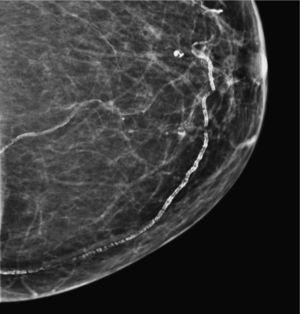

Calcificaciones vasculares (fig. 2)El depósito de calcio en el perímetro de las fibras elásticas de las paredes arteriales genera calcificaciones densas, lineales y paralelas que siguen el trayecto tortuoso de un vaso5.